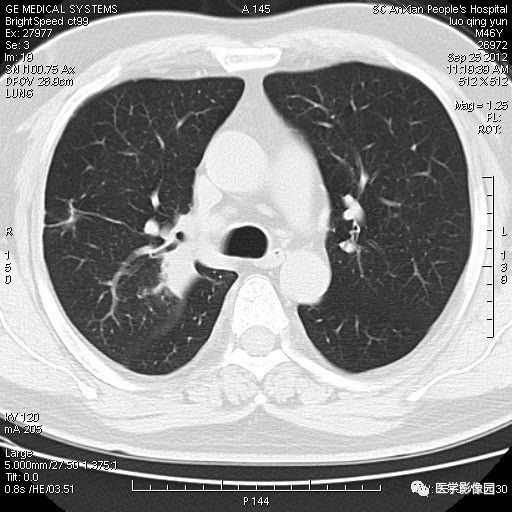

影像学表现:右上肺见不规则团块状高密度阴影,略有分叶级毛刺,边缘模糊,邻近胸膜增厚,增强扫描呈轻中度强化。

诊断结果:右上肺炎性假瘤

本病影像学表现无绝对特征性。单发多见,多位于肺表浅部位,多呈圆形或椭圆形,直径多在2-5cm或更大;多有假包膜,边缘多清晰光整,有时也毛糙,并可有分叶或毛刺;邻近胸膜局限性增厚、牵拉,病灶边缘呈桃尖样突起即桃尖征(尖端指向胸膜);增强扫描多呈中度均匀强化,持续时间较长。亦可显著强化。